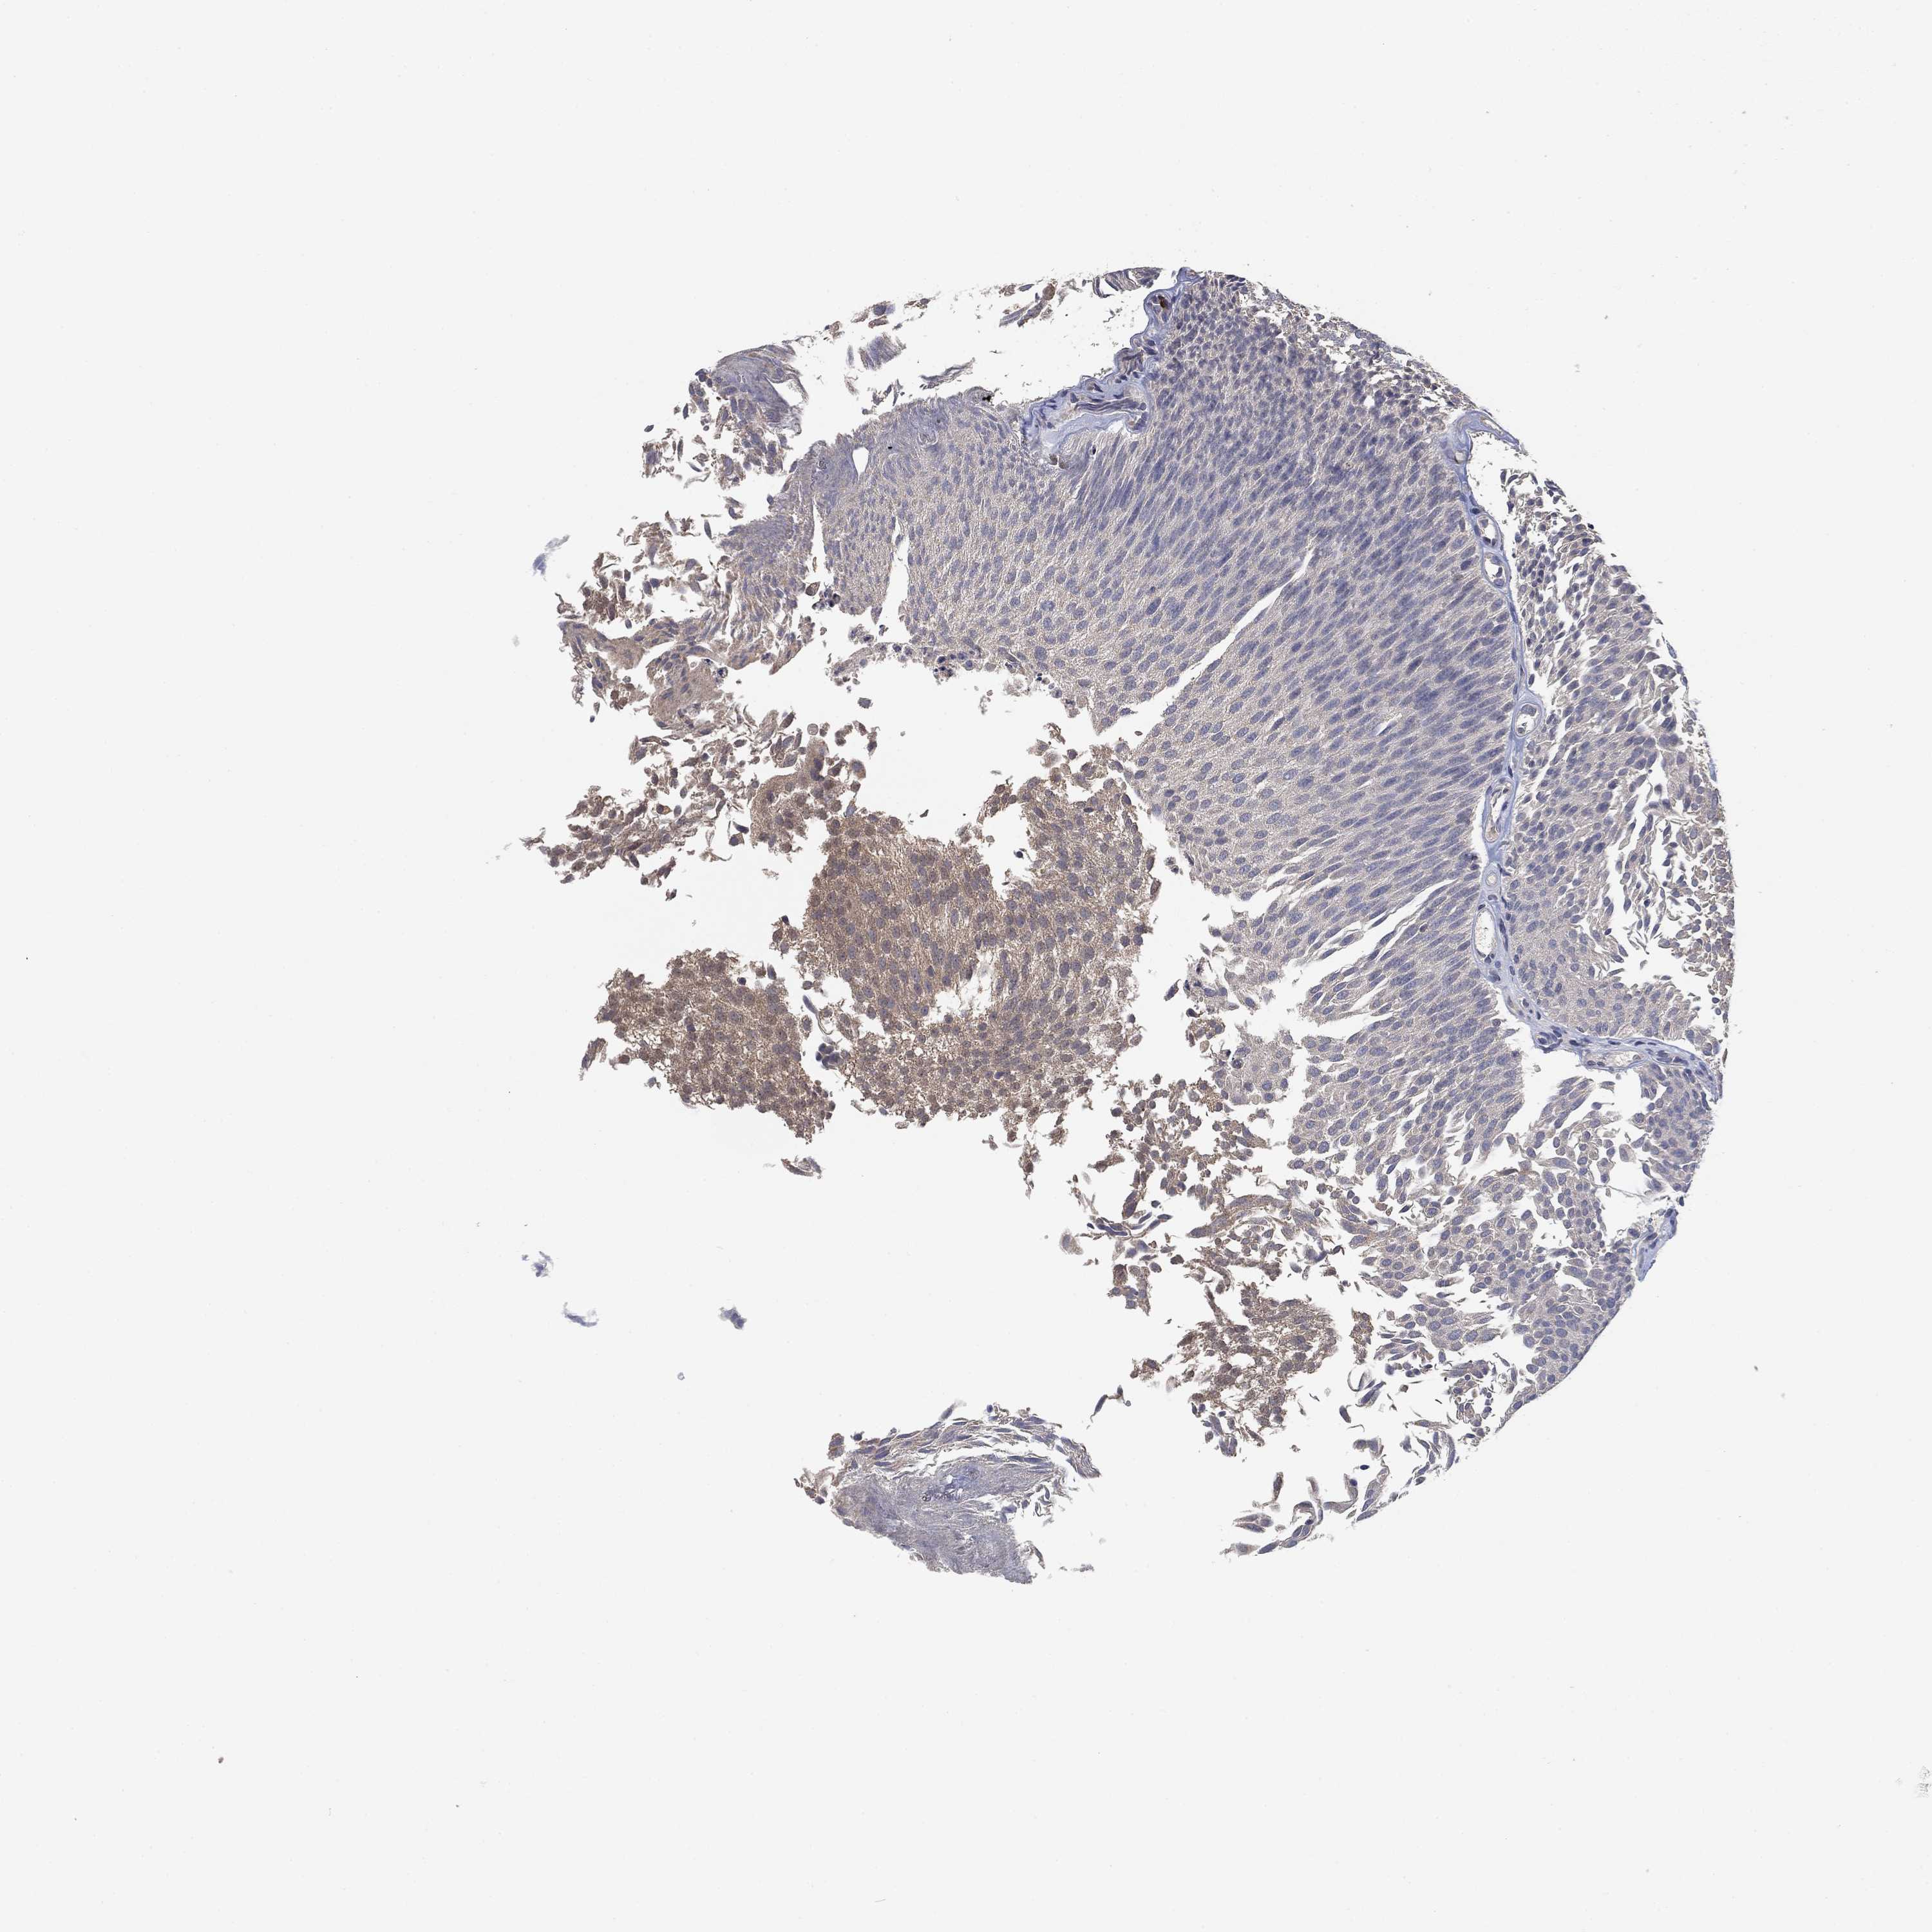

UROTHELIAL CANCER - Protein expressioni

A mouse-over function shows sample information and annotation data. Click on an image to view it in a full screen mode. Samples can be filtered based on level of antibody staining by selecting one or several of the following categories: high, medium, low and not detected. The assay and annotation is described here.

Note that samples used for immunohistochemistry by the Human Protein Atlas do not correspond to samples in the TCGA dataset.

Antibody stainingi

Antibody staining in the annotated cell types in the current human tissue is reported as not detected, low, medium, or high, based on conventional immunohistochemistry profiling in selected tissues. This score is based on the combination of the staining intensity and fraction of stained cells.

Each image is clickable and will lead to virtual microscopy that enables deeper exploration of all samples and also displays staining intensity scores, fraction scores and subcellular localization as well as patient and tissue information for each sample.

Antibody HPA023391

Urothelial carcinoma, Low grade